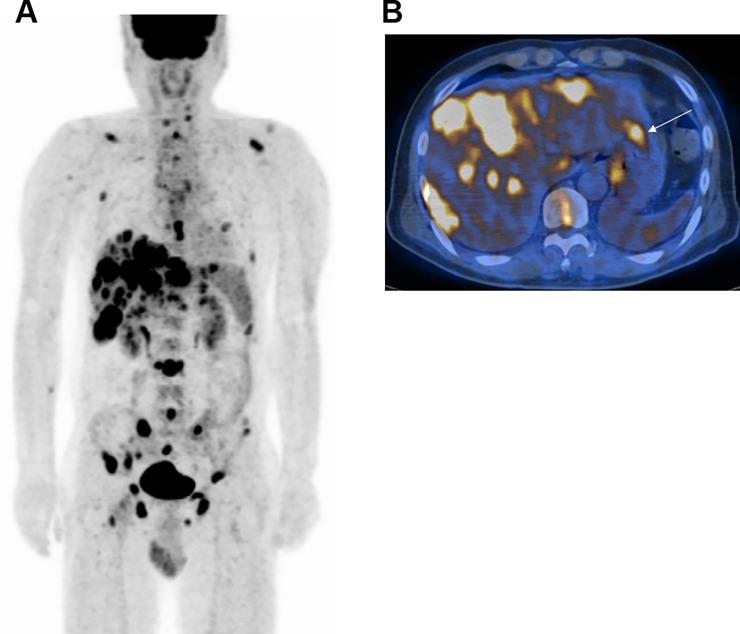

When subjects without a known malignancy present with suspicious skeletal lesions, differential diagnosis and primary cancer identification is important. Here, we investigated the role of FDG PET/CT in this clinical situation.

We enrolled 103 patients with no known malignancies who were referred for FDG PET/CT because of bone lesions that were suspicious for cancer metastasis. Each extra-skeletal FDG lesion was categorized as consistent with primary cancer or with metastasis based on the distribution and pattern of all abnormal lesions in the individual.

Final diagnosis revealed that bone lesions represented cancer metastasis in 75 patients (72.8%). In the remaining 28 patients (27.2%), they were from other causes including multiple myeloma or lymphoma, malignant primary bone tumor, and benign bone disease. PET/CT indicated a primary cancer in 70 patients (68.0%). This was the correct primary site in 46 cases and the incorrect site in 13 cases (including 6 cases with cancer of unknown primary, CUP). In the remaining 11 cases, the bone lesions were due to other causes. PET/CT did not indicate a primary cancer in 33 patients (32.0%). Of these cases, 17 did not have a primary cancer, 8 had CUP, and 8 had primary cancers that were missed. Thus, PET/CT had a sensitivity of 61.3% and specificity of 60.7% for primary cancer identification in the entire population. Excluding patients with CUP, PET/CT sensitivity was 75.4%. PET/CT also provided information useful for recognizing multiple myeloma and benign bone disease as the cause of the skeletal lesions.

In patients without known malignancies with suspected skeletal cancer metastasis, FDG PET/CT can help identify the primary cancer and provide useful information for differential diagnosis.

当没有已知恶性肿瘤的患者出现可疑的骨骼病变时,鉴别诊断和确定原发性癌症非常重要。在这里,我们研究了 FDG PET/CT 在这种临床情况下的作用。

我们招募了 103 名没有已知恶性肿瘤的患者,由于骨骼病变疑似癌症转移,他们被转介进行 FDG PET/CT。根据个体中所有异常病变的分布和模式,将每个骨骼外 FDG 病变归类为与原发性癌症一致或与转移一致。

最终诊断显示,75 名患者(72.8%)的骨骼病变代表癌症转移。在其余 28 名患者(27.2%)中,他们患有其他疾病,包括多发性骨髓瘤或淋巴瘤、恶性原发性骨肿瘤和良性骨疾病。PET/CT 在 70 名患者(68.0%)中提示原发性癌症。在 46 例中,这是正确的原发性部位,在 13 例中是错误的部位(包括 6 例癌症未知原发部位,CUP)。在其余 11 例中,骨骼病变是由其他原因引起的。在 33 名患者(32.0%)中,PET/CT 未提示原发性癌症。在这些病例中,17 例没有原发性癌症,8 例患有 CUP,8 例原发性癌症被遗漏。因此,PET/CT 对整个人群原发性癌症的识别具有 61.3%的敏感性和 60.7%的特异性。排除患有 CUP 的患者后,PET/CT 的敏感性为 75.4%。PET/CT 还提供了有助于识别多发性骨髓瘤和良性骨疾病作为骨骼病变原因的有用信息。

在没有已知恶性肿瘤且疑似骨骼癌症转移的患者中,FDG PET/CT 可以帮助识别原发性癌症,并为鉴别诊断提供有用信息。